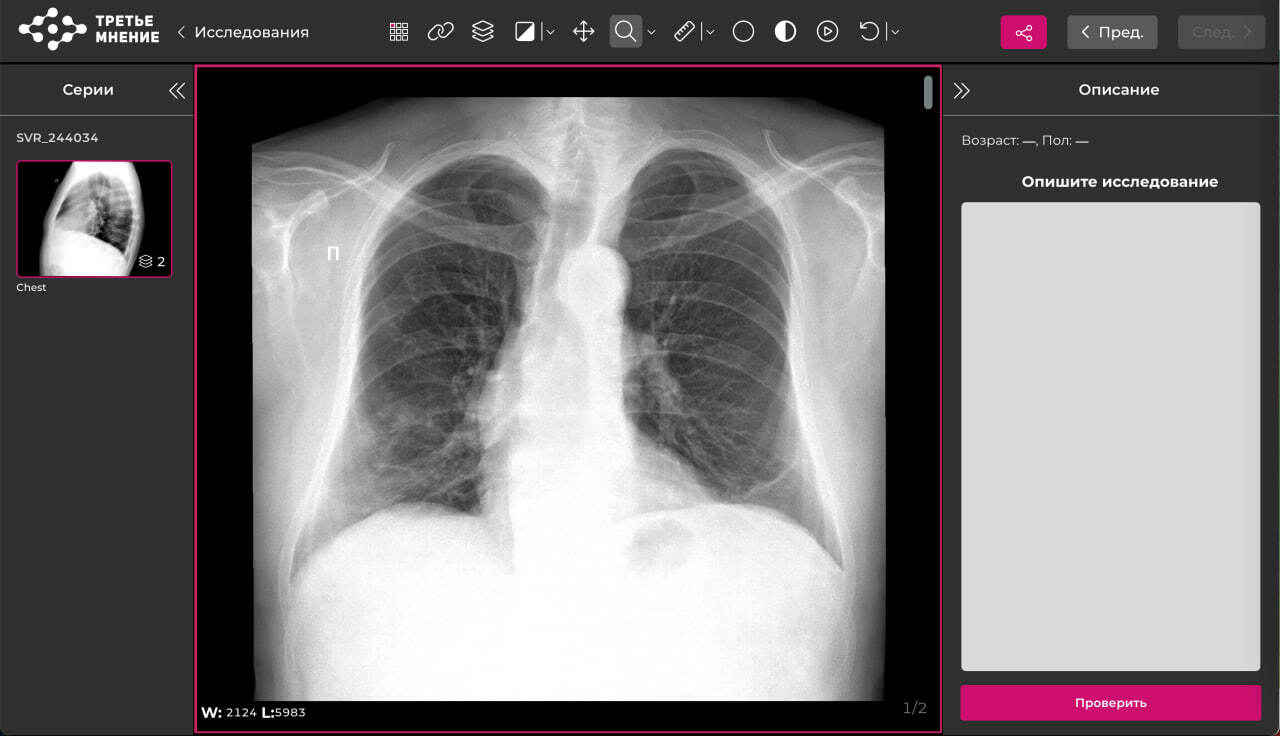

Направление "Рак лёгкого"

Критерии протокола по РГ ОГК:

1. Определено наличие очаговой/фокусной тени (обнаружены или не обнаружены)

Если обнаружены:

- Указана локализация 3-х наиболее крупных очаговых/ фокусных теней. При наличии 2-х проекций - локализацию указать по долям и сегментам, если в одной проекции, то по отделам (верхний/средний/нижний и внутренний/наружный)

- Перечислены признаки, указывающие на злокачественность/доброкачественность (при наличии таковых. Если их нет, указано, что отсутствуют)

- Выставлен дифференциальный ряд

- Даны рекомендации по дальнейшей маршрутизации пациента

Если не обнаружены:

- Описано, какие рентгенологические признаки присутствуют на исследовании

2. Если на снимке нет признаков патологий:

- Указано, что снимок без видимых признаков патологий